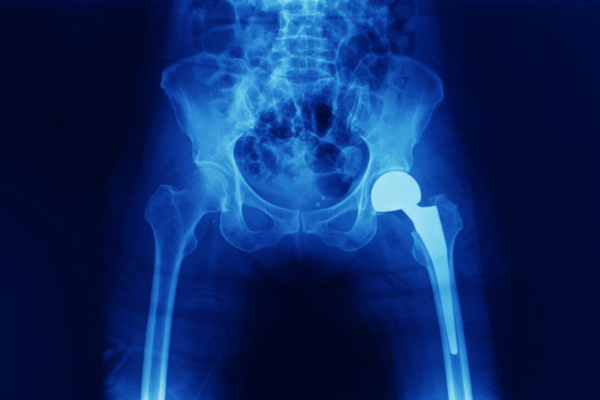

Hip Replacement Surgery is a procedure where a broken hip joint is replaced with a prosthetic implant to restore function and relief from pain. Dr. Patage, a specialist in the industry for over 15 years, is a reputable expert to approach for Hip Replacement in Akshayanagar, Bangalore.

Implant Placement